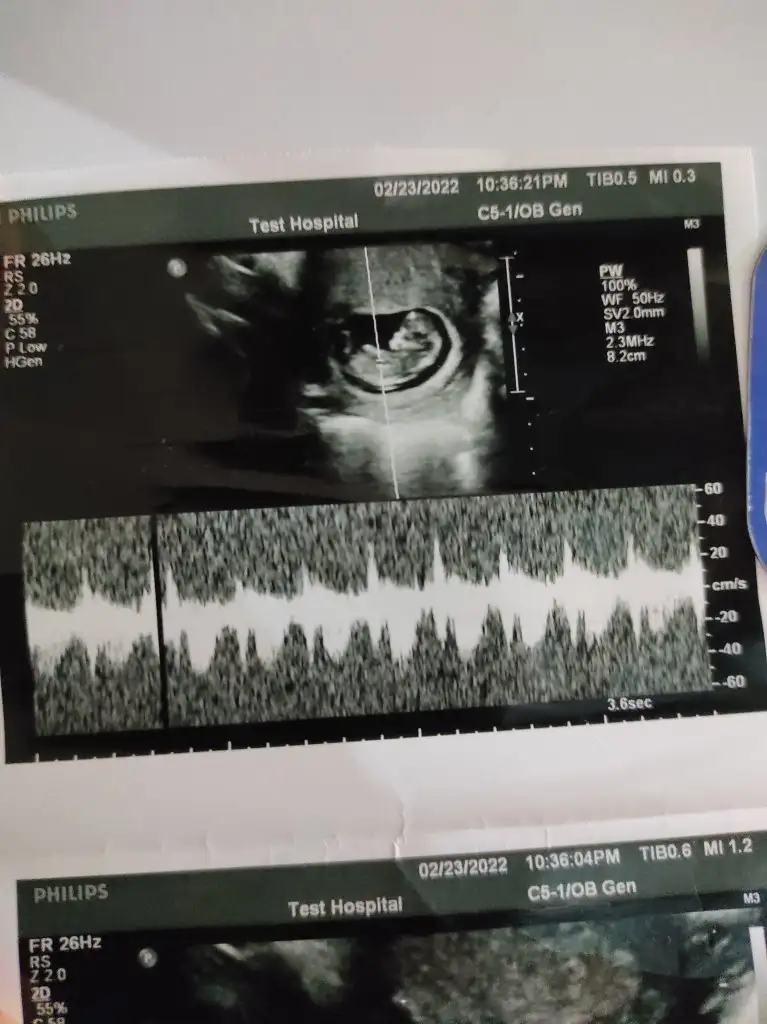

Kuzum bazı usg fotoğraflarında yazmıyor seninkinde de göremedim, bende mesela 3 ayrı foto veriyor ya kalp atışına baktığı bir fotoğraf var orda yazıyor diğerlerinde yazmıyor. Onun ayrı ölçümü olduğu İçin sanırım hepsinde yok.

Video atabilseydik keşkeKuzum bazı usg fotoğraflarında yazmıyor seninkinde de göremedim, bende mesela 3 ayrı foto veriyor ya kalp atışına baktığı bir fotoğraf var orda yazıyor diğerlerinde yazmıyor. Onun ayrı ölçümü olduğu İçin sanırım hepsinde yok.